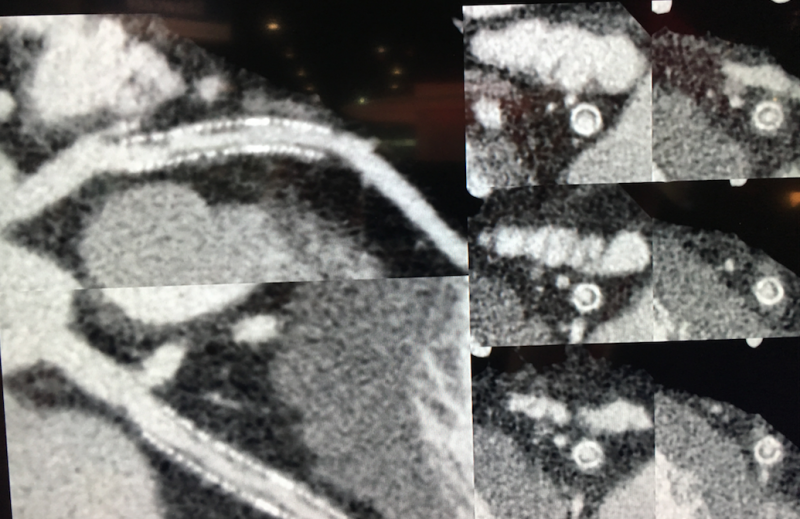

The Aquilion Precision was unveiled for the first time at the 2017 Radiological Society of North America (RSNA) meeting and was cleared by the FDA in April 2018. It is unique in that it is the first CT system to offer a 0.25 mm resolution, rather that the standard 0.5 mm resolution on most of today’s scanners. It is capable of resolving coronary anatomy as small as 150 microns, providing CT image quality with resolution typically seen only in cath lab angiography. This enables better visualization of tiny structures, such as the composition of coronary plaques, stent struts and smaller coronary vessels that are generally difficult to see on CTA scans. The resolution may aid in better plaque assessments, including clearer identification of vulnerable plaques, visualizing broken stent struts, and identification of a specific vendor’s stents based on strut design in vessels.

The Precision uses a newly designed detector to provide more than twice the resolution of 0.5 mm systems. The scanner offers dose efficiency with detector channels that are only 0.25 mm thick. It also has improvements in scintillator quantum efficiency, detector circuitry and other components. The system features the industry’s smallest focal spot tube, at 0.4 x 0.5 mm, and the industry’s first routine 1,024 x 1,024 reconstruction matrix.